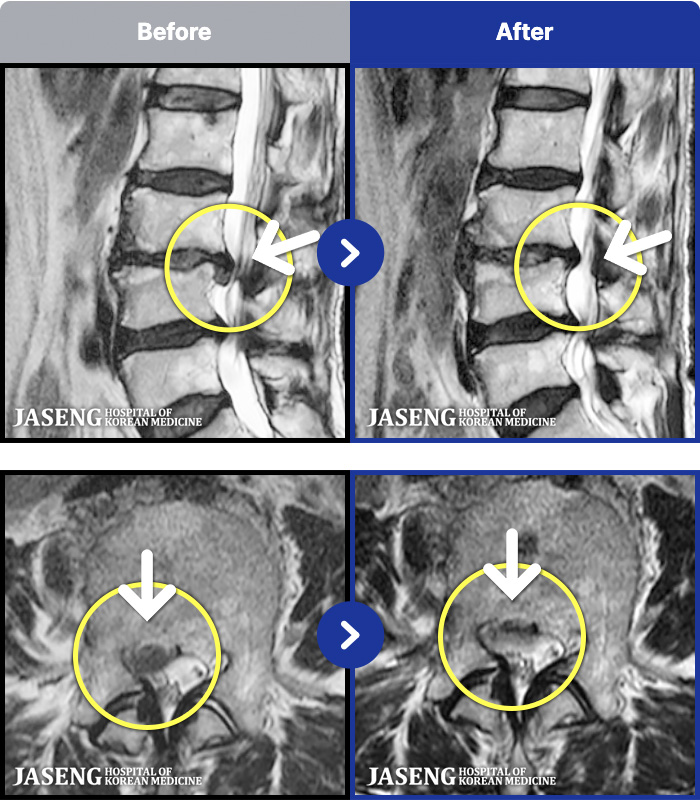

MRI ġ

1,237 MRI ũ ʸ Ȯϼ.